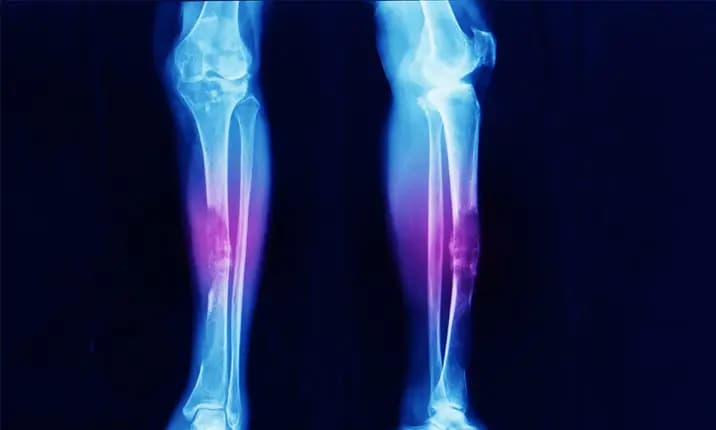

Sarcoma diagnosis necessitates a combination of imaging, biopsy, and clinical evaluation:

Following diagnosis, the tumor is staged and graded (low, intermediate, or high grade) to determine its aggressiveness, size, depth, and spread.

The mainstay of treatment for the majority of localized sarcomas is surgery. Removing the tumor while leaving a visible margin of healthy tissue is the aim. When it is feasible, limb-sparing surgery is preferred to amputation for extremity sarcomas.